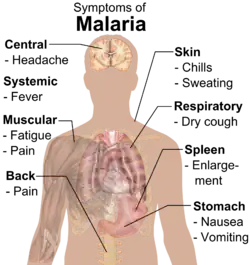

Signs and symptoms

Adults with malaria tend to experience chills and fever – classically in periodic intense bouts lasting around six hours, followed by a period of sweating and fever relief – as well as headache, fatigue, abdominal discomfort, and muscle pain.[22] Children tend to have more general symptoms: fever, cough, vomiting, and diarrhea.[22]

Initial manifestations of the disease—common to all malaria species—are similar to flu-like symptoms,[23] and can resemble other conditions such as sepsis, gastroenteritis, and viral diseases.[11] The presentation may include headache, fever, shivering, joint pain, vomiting, hemolytic anemia, jaundice, hemoglobin in the urine, retinal damage, and convulsions.[24]

The classic symptom of malaria is paroxysm—a cyclical occurrence of sudden coldness followed by shivering and then fever and sweating, occurring every two days (tertian fever) in P. vivax and P. ovale infections, and every three days (quartan fever) for P. malariae. P. falciparum infection can cause recurrent fever every 36–48 hours, or a less pronounced and almost continuous fever.[25]

Symptoms typically begin 10–15 days after the initial mosquito bite, but can occur as late as several months after infection with some P. vivax strains.[22] Travellers taking preventative malaria medications may develop symptoms once they stop taking the drugs.[22]

Severe malaria is usually caused by P. falciparum (often referred to as falciparum malaria). Symptoms of falciparum malaria arise 9–30 days after infection.[23] Individuals with cerebral malaria frequently exhibit neurological symptoms, including abnormal posturing, nystagmus, conjugate gaze palsy (failure of the eyes to turn together in the same direction), opisthotonus, seizures, or coma.[23]